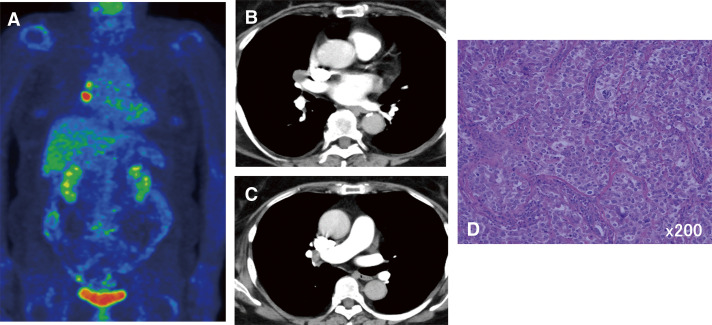

Case presentation: Case 1 was a 50-year-old woman diagnosed with ovarian cancer with mediastinal lymph node metastasis. After 4 courses of chemotherapy, a total hysterectomy, omentectomy, and mediastinal lymph node dissection were performed simultaneously. The patient is still alive 58 months after surgery. Case 2 was a 68-year-old woman who underwent a total hysterectomy after chemotherapy for endometrial cancer with multiple lymph node metastases. Forty-two months after surgery, mediastinal lymph node dissection was performed for metastasis of uterine cancer. She is still alive 75 months after surgery. Case 3 was a 69-year-old woman who underwent a hysterectomy for endometrial cancer. One year after surgery, she underwent thoracoscopic hilar and mediastinal lymph node dissection due to metastasis. Thirty-nine months have passed with no recurrence. Aggressive local control, particularly surgical resection of isolated hilar mediastinal lymph nodes in gynecological cancer, may contribute to prolonging patient survival.